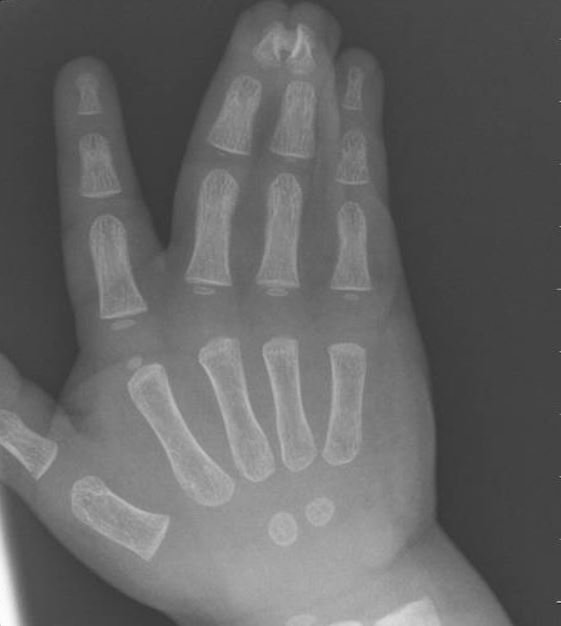

Syndaktyli kan diagnostiseras utan bilddiagnostiska undersökningar. Röntgenbilder tas från fall till fall för att ytterligare utreda en eventuell benavvikelse.